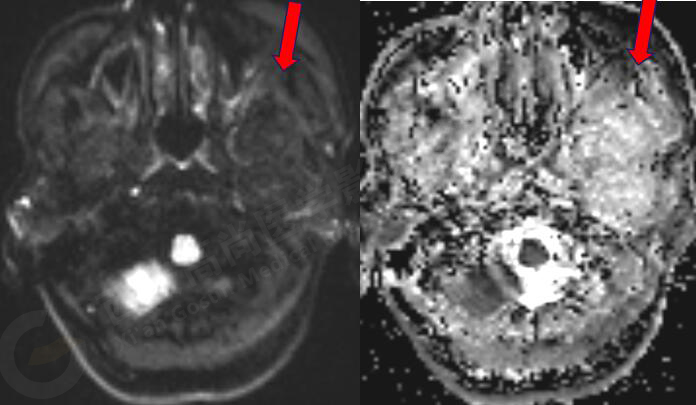

女,58歲,左側(cè)咀嚼肌間隙腫塊,鄰近翼板外側(cè)骨質(zhì)破壞;左側(cè)下頜升支內(nèi)側(cè)占位,皮質(zhì)旁骨軟骨來源。

MR圖像

MR診斷

左側(cè)翼腭窩、顳下窩占位,左側(cè)腮腺受壓變形,頸內(nèi)動脈稍受壓,考慮軟骨組織來源、良性病變。

此腫瘤位于左側(cè)翼腭窩、顳下窩,各序列均呈低信號,與翼突內(nèi)外側(cè)板、下頜骨關(guān)系密切,鄰近下頜骨骨皮質(zhì)破壞,DWI像上呈較高信號,呈不均勻中度強化,因此考慮軟骨來源或肌纖維來源,良性可能性大。